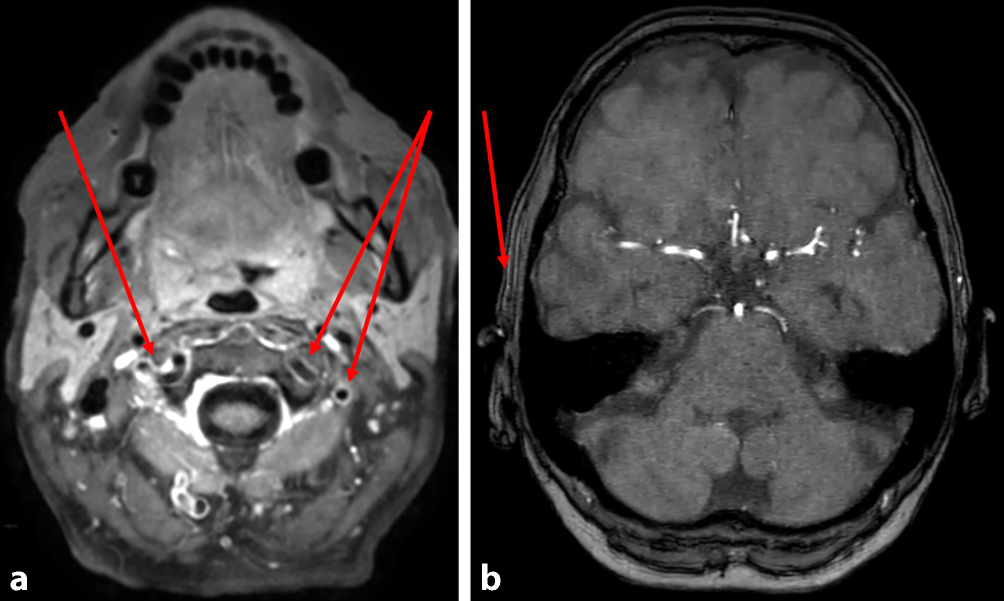

Bei Aufnahme beträgt die Sehschärfe rechts Handbewegungen, bei Entlassung nulla lux. Die Fundoskopie beschreibt eine ödematöse, blasse Papille, eine Tortuositas der Gefäße, eine Ischämiebande der inferioren Hälfte und einen Hemizentralarterienverschluss. CRP und BSG sind bei Aufnahme und im Verlauf normal (Tab. 1). CCT mit Angiographie an Tag 1 ohne Vaskulitis-typische Veränderungen. Die cMRT mit Kontrastmittel (KM) an Tag 3 weist eine Vaskulitis mit Manifestation in den Aa. temporales superficiales nach (Abb. 1). Die rechtsseitige A. temporalis superficialis sowie der Ramus frontalis der kontralateralen Arterie sind verschlossen. Die [18F]-FDG-PET/CT vom selben Tag ergibt Stoffwechselsteigerungen insbesondere in der A. vertebralis beidseits (Abb. 2) sowie geringer in der A. carotis interna, in der Bauchaorta und in den Beinarterien, gut vereinbar mit Riesenzellarteriitis. Eine Temporalisbiopsie wurde von der Patientin abgelehnt.

Abb. 1

a cMRT, Sequenz T1 Black Blood transversal mit Kontrastmittel (KM). Deutliches KM-Enhancement der Vertebralarterien (Pfeile); b Sequenz 3D „time of flight“ (TOF), fehlendes Flusssignal der A. temporalis superficialis rechts (Pfeil)